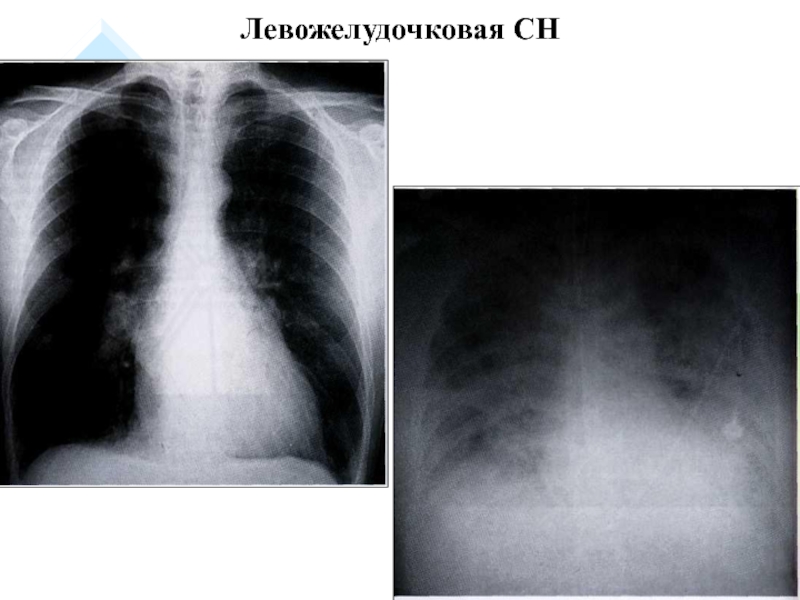

Слайд 13Левожелудочковая СН

Левожелудочковая СН

Слайд 14Отек легких при ЛСН

Отек легких при ЛСН

1. Левожелудочковая СН: ↑ давление

крови в легочных венах, сосудах малого круга, в правом желудочке

(застой) → сердечная астма, отек легких.